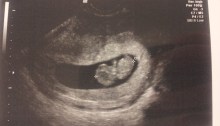

Sonogram

Here it is… the picture we’ve all been waiting for. Here’s a secret, don’t tell Stephanie I told you… she took another pregnancy test AFTER her original pregnancy test… just to make sure. And, I don’t even think she really thought that was all real until THIS. The picture! From what we learned today, the…